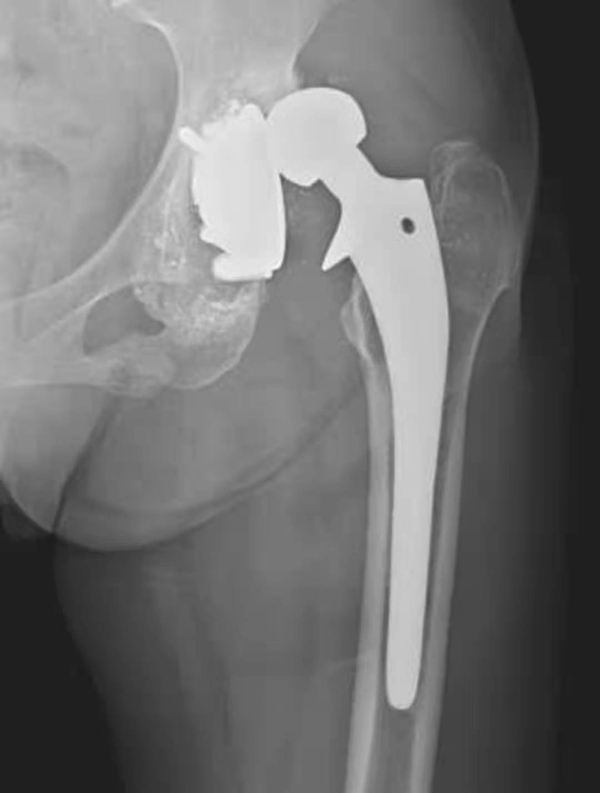

图2 无菌性松动

平片,示右侧股骨上段骨质疏松,人工股骨柄周围明显骨质吸收,透亮带明显增宽,髋臼杯位置未见改变